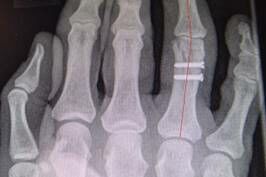

Diagnose: Mehrfragmentfraktur am Ringfingergrundglied rechts (s. Abb. 1)

Die Klägerin war gestürzt und hatte sich die rechte Hand verletzt. Die ärztliche Erstversorgung erfolgte am Unfalltag in der beklagten Klinik. In den Röntgenaufnahmen der rechten Hand wurde eine Mehrfragmentfraktur am Ringfingergrundglied diagnostiziert, die 10 Tage später offen reponiert und mit 2 Schrauben osteosynthetisch stabilisiert wurde.